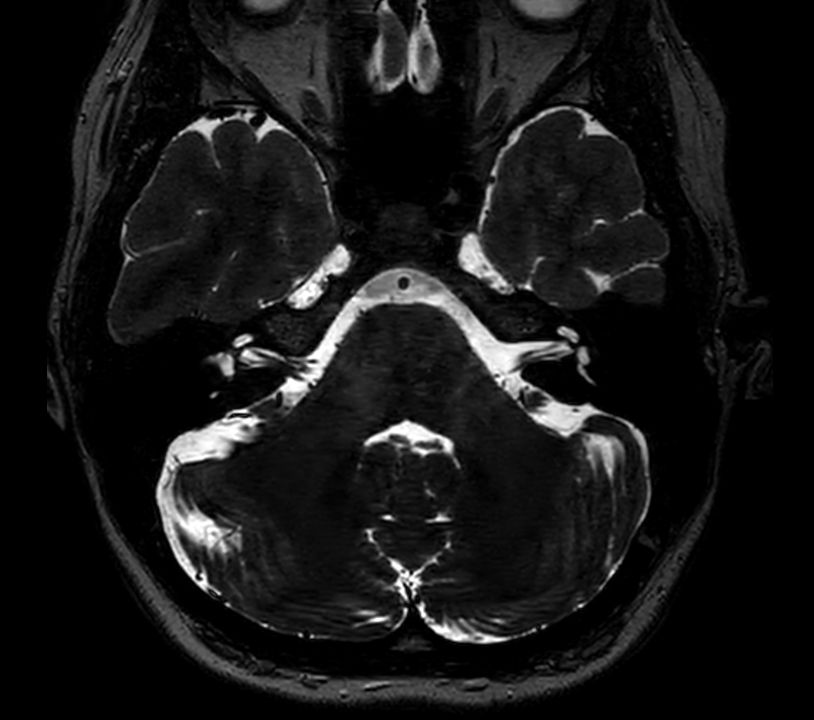

Axial 3D T2w TSE DRIVE

Fast and high quality 3D imaging for Brain and IAC. AI based SmartSpeed is utlized to shorten scan time without compromise in image quality. Advanced 3D TSE imaging technique are used to acquire high resolution data in multiple directions in only one single scan. Addition of DRIVE enhances fluid visualization for IAC imaging, while providing high contrast-to-noise and high signal-to-noise ratio simultaneously. SWIp 3D susceptibility weighted brain imaging is added, offering a high sensitivity to enhance contrast for deoxygenated (venous) blood or calcium deposits.